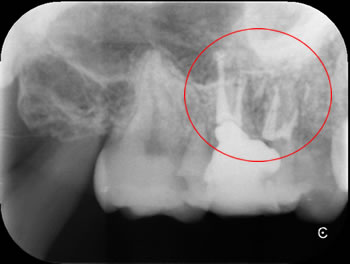

初診時のレントゲンです。

根管充填したところです。薬が4つはいっています。赤丸がMB2です。